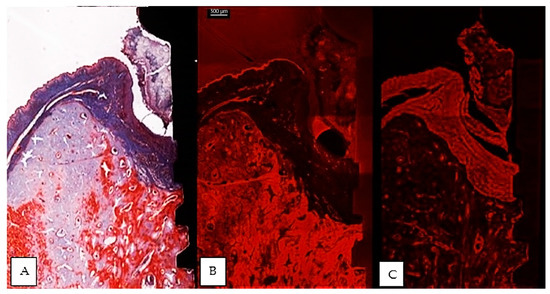

Figure 3.

Comparative images of the same implant, between a thin section in light microscopy, Masson Goldner Anilin blue stain (A), same thin section in CLSM (B) and a thick section in CLSM (C). Morphological preservation of tissular integrity is better seen in the thick section. (implant #5, buccal aspect, bar measure for all three images is 300 µm).

The usual light microscopy technique using pentachrome stains revealed good tissue morphology preservation; however, the opacity of the metallic implant made it difficult on some of the specimens to properly identify the implant shoulder. The CLSM thin sections were easier to scan, having a flatter surface, yet the grinding to a thin section led to minor tissue cracks in the bone component (Figure 3A,B). Furthermore, the use of mounting medium and coverslip on the thin sections induced an additional decrease in contrast, altering the quality of soft tissue morphology in the thin sections (Figure 3A,B). In both thin and thick sections, the implant shoulder was easily identifiable, except in the thick sections where the implant was lost during histological processing. The peri-implant sulcus is shallower in non-ligated specimens than in ligated ones, the bone is in contact with the implant surface and the soft tissue is in contact with the healing abutment (Figure 4). Infiltrated connective tissue (ICT) was present in contact with bone and implant (Figure 5). However, it is important to mention that the cellularity of the ICT was not visible under CLSM; therefore, LM seemed better suited for the assessment of the ICT. Epithelial lining integrity was broken, more pronounced on the oral aspect, making the identification of landmarks like aJE extremely difficult (Figure 6). This comes not as a surprise under the severe inflammation circumstances found in peri-implantitis, as this landmark is poorly identifiable even on LM. In these areas of integrity loss, the highly inflamed soft tissue was identified in direct contact with the bone and implant (Figure 7). Regarding the soft tissues, the epithelial covering is clearly identifiable on both types of evaluation (LM and CLSM).

In addition, the significant additional expense involved in the preparation of analyzable stained histological specimens and their susceptibility to errors need to be taken into account [54]. These findings must be considered critically, especially when preparing thinner stained sections. On the other hand, despite an increasing accuracy of the potentially visible histological details, very thin sections proved sometimes disadvantageous with respect to the handling of the specimens, the complexity of the fixation procedures and the duration of the grinding, and the creation of artifacts that could jeopardize the quality of the observations. In sections that are reduced to approx. 30 μm, scratches on the surface, extrusion of the implanted material, cracks, areas of sheer tissue loss, and uneven thicknesses may result in poor cellular detail, as noted in our study on the “thin” sections. [31] (Figure 3A,B). Many researchers agree that great technical skills are needed in obtaining satisfactory thin sections by maintaining parallelism during the grinding procedures. It is also known that during grinding the hard metal normally is depressed more on the sandpaper than the adjacent softer tissue, and this causes the surrounding tissue to abrade faster than the metal. Yet, the undecalcifed technique has been used widely for oral implants [55,56,57,58], despite the fact that processing artifacts in the histological very thin sections are still common [55].